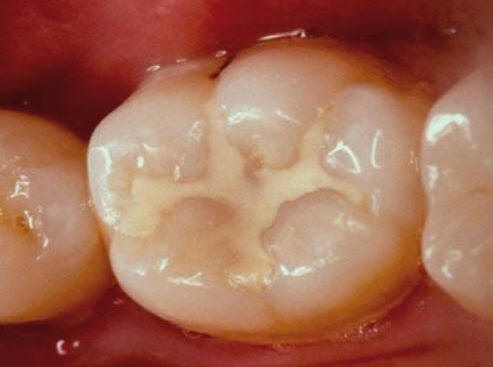

Una morfología de la fisura estrecha, con forma de botella de "Coca-Cola" genera un nicho ecológico ideal para la colonización de cualquier bacteria productora de ácidos. Al no poder remover en forma períodica dicho biofilm de una zona tan estrecha, el ataque ácido genera una lesión cariosa en la dentina, con un aspecto de esmalte intacto a la inspección visual, o sea un típico código 3 y 4 de ICDAS Completo. (Caries Moderada para el ICDAS COMBINADO)

Por este motivo es importante realizar el sellado de las fosas y fisuras de molares y premolares cuando comienza su erupción dentaria, como método de prevención eficaz de caries.

El examen visual debe emprenderse con los dientes completamente secos y con una buena iluminación.  El uso de amplificación de imagen también puede ayudar en el diagnóstico. El uso de una sonda se restringe al levantamiento de placa y detritos de comida.

El diente al lavarse y secarse con la jeringa triple deja expuesto esmalte blanquecino escarchado o opaco que delata un proceso de desmineralización, debido a que el agua se evapora de los microporos. Ver círculos rojos

Una mancha oscura de dentina que se observa a través del esmalte intacto,  adyacente a la fosa y reborde marginal,  indica la presencia de desmineralización. (Imagen 0229)